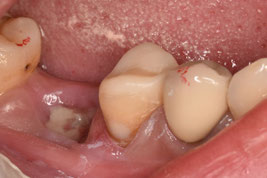

2日目にファイバーコアを植立しました。

軸面の健全歯質を大幅に残したうえで、オーバーレイの形態で修復しました。インジェクションモールディング法を応用しております。直接修復なので、海外からの来院であっても、短期滞在で対応可能です。

1回法による根管治療で進めました。1回法だと3時間くらい口を開けっ放しになるので、患者さんは辛いと思います。ご協力いただき大変恐縮です。

ダイレクト修復に完全移行してから、歯冠形成が大きく変わりました。アンダーカットを積極的に付与するようになり、形成のキレイさを気にせず、健全歯を最大限残す形態になりました。